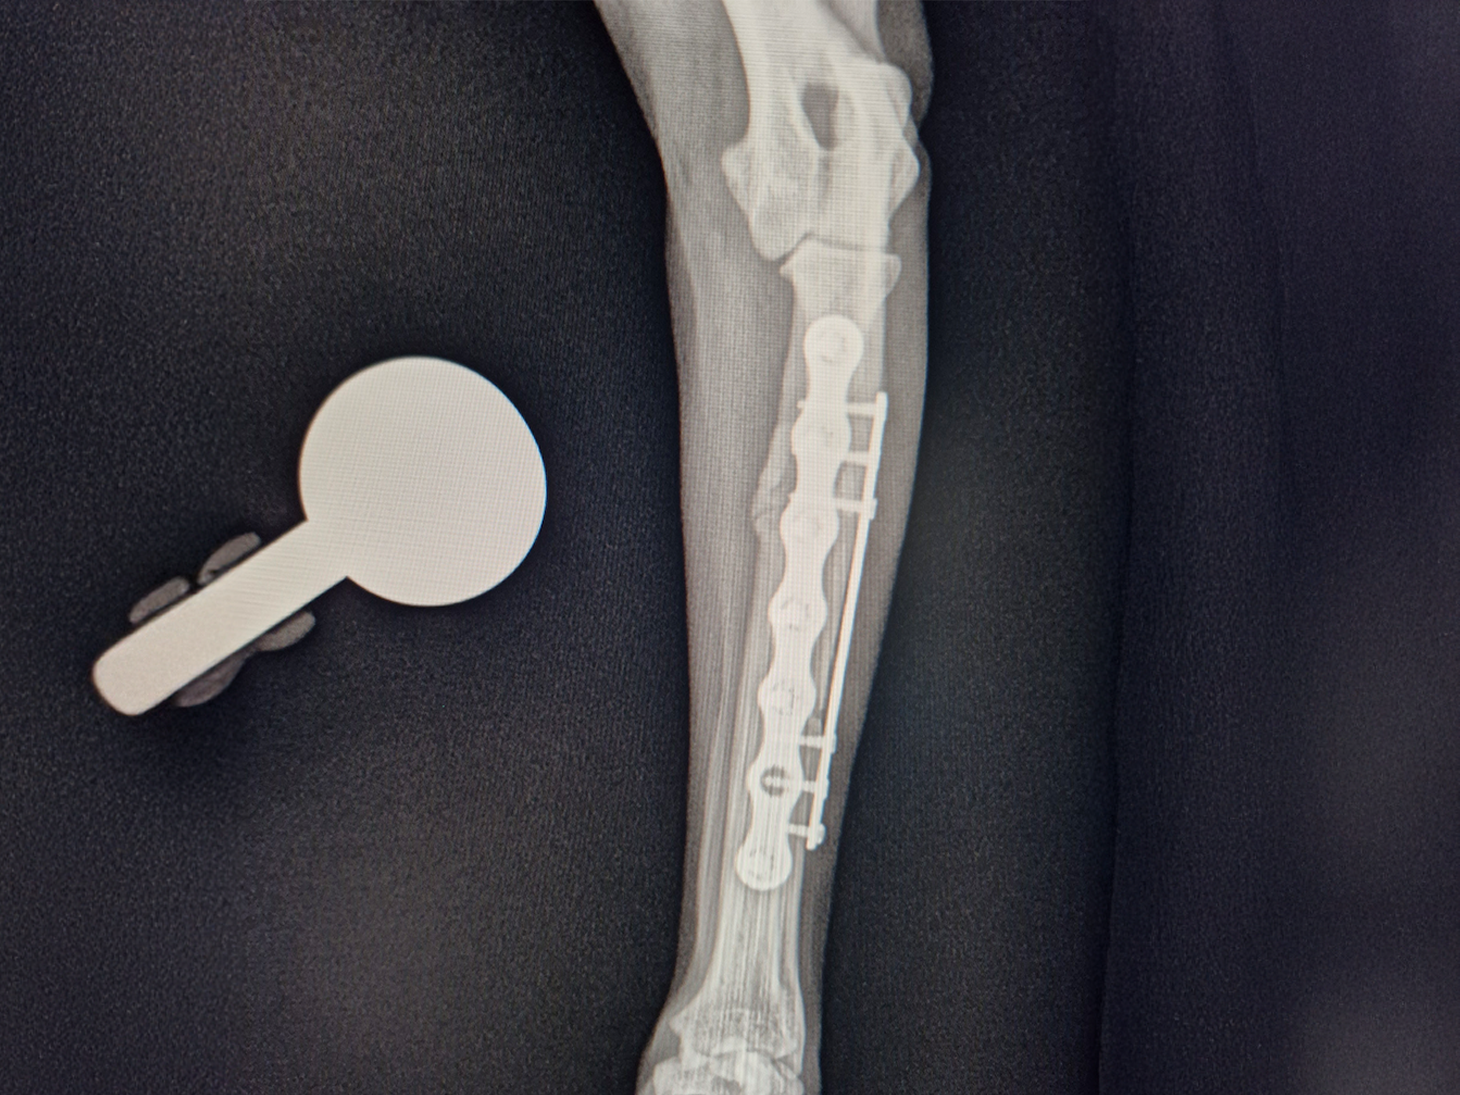

The complex, dual-bone injury required a sophisticated approach performed by Dr. Ditte Skytte.

- The severely comminuted radius fracture was stabilized using a 2.0 mm titanium LeiLOX plate, specifically chosen to manage the comminution in combination with a supportive repair of the ulna.

- The ulna fracture was addressed with our innovative 1.0 mm titanium LeiLOX plate, secured by 1.3 mm locking screws. This combination provided robust, yet minimally disruptive, fixation crucial for a small patient. The surgical site was thoroughly flushed, and the patient received Cefazolin both perioperatively and for three days post-op to manage the open wound.

- X-Ray Confirmation: The surgery sites were fully healed, with no discomfort upon palpation. X-rays showed advanced healing with significant callus formation and all implants intact.

Implant Used: LeiLOX Locking System (1.5-2.0 mm and 1.0 mm - Titanium with 1.3 mm screws)